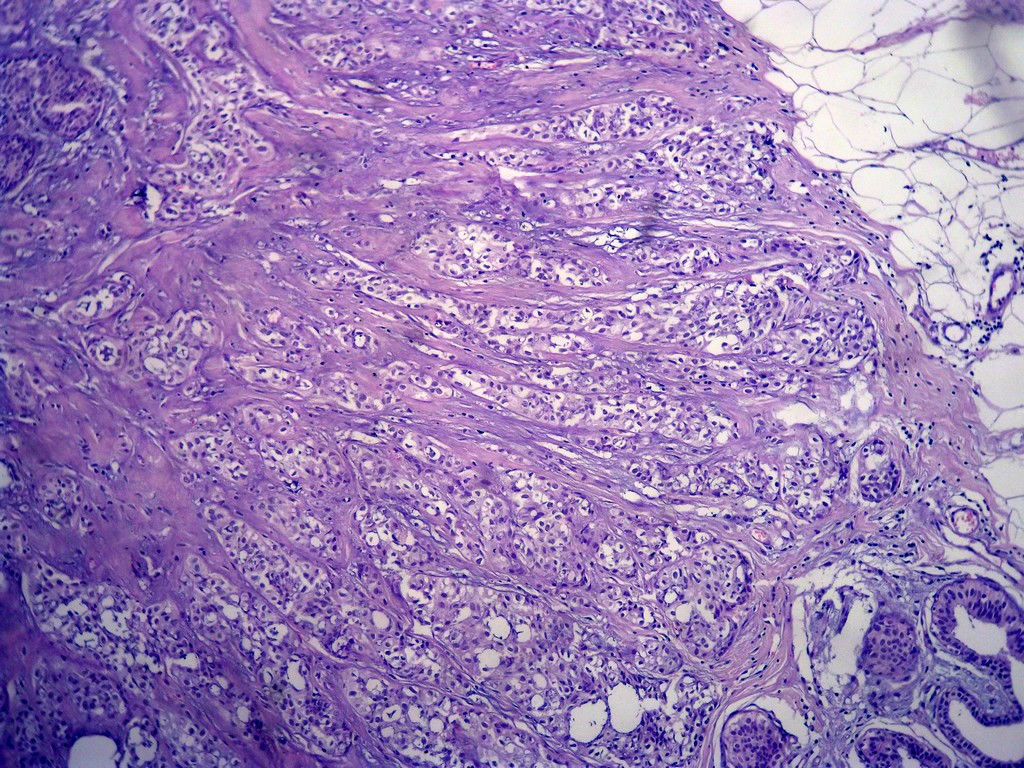

今天的一例术中冰冻。女,49岁,乳腺肿块。人气不旺,换个标题

腺病?癌?其他?(12楼常规,24楼免疫组化及会诊结果)图1

标签:浸润性导管癌 分泌癌 硬化性腺病

多谢强版主,这可是俺亲自全程操作的一张片子,俺的一点小经验是“组织要干”,“冷冻要快”,这个病例有点考验俺的神经,发上来听听高手们的意见。大体是乳腺组织一块,切面见一质硬结节,直径2cm,边界欠清,切面灰白色。强版别光夸片子漂亮啊,留下你的高见才放行

1. Most likely no invasive cancer

2 Sclerosing adenosis

3 Ductal epithelial hyperplasia

4. Bundles d Smooth muscle?

导管是乎可见双层上皮,部分上皮增生并有一定异型,考虑硬化性腺病,待石蜡。

导管可见双层上皮,部分上皮增生并有一定异型,考虑硬化性腺病

腺体与腺体之间的对比差异太大,不放心,不除外是癌,如果是我的病例,再次取材冰冻

浸润性导管癌。冰冻切片的诊断是很困难,直接诊断癌风险很大,但是在明显正常的导管间这种成片、成巢有腔的细胞团块也不是良性的表现,有的还似乎有围绕正常导管生长的倾向。诊断ADH还可以,但是不能归到任何一种DCIS的生长方式里。这例值得我好好学习。